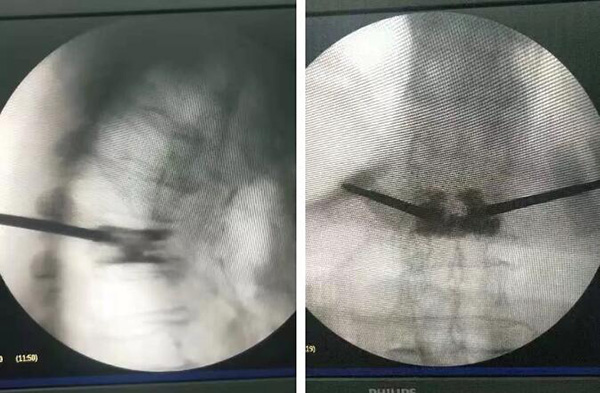

10月29日手術現(xiàn)場

廣安醫(yī)院脊柱科戈才華主任親自主刀,在局部麻醉的情況下,為陳爺爺實施了“胸7/腰1椎體壓縮性骨折經(jīng)經(jīng)皮穿刺球囊擴張椎體成形術。”

經(jīng)過一個半小時,手術順利完成。術后脊柱科醫(yī)護人員對陳爺爺精心護理,“手術后最開始幾天,我父親情緒很不穩(wěn)定,你們的主任、醫(yī)生、護士長都積極安慰鼓勵她,我父親恢復的這么好多虧了你們,真心的感謝你們醫(yī)院”陳爺爺?shù)膬鹤舆@樣說。